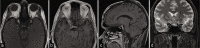

Case description: We describe a case of CAPNON at the right posterior clinoid process with involvement of the right oculomotor nerve in a 38-year-old male. Computed tomography demonstrated an amorphous mass which had intermediate to low T1 and T2 signal on magnetic resonance imaging. The oculomotor nerve was compressed with sign of atrophy. The patient underwent maximal surgical debulking for progressive symptoms of worsening pain and ophthalmoplegia. Postoperatively, the patient's symptoms were stable but did not improve.